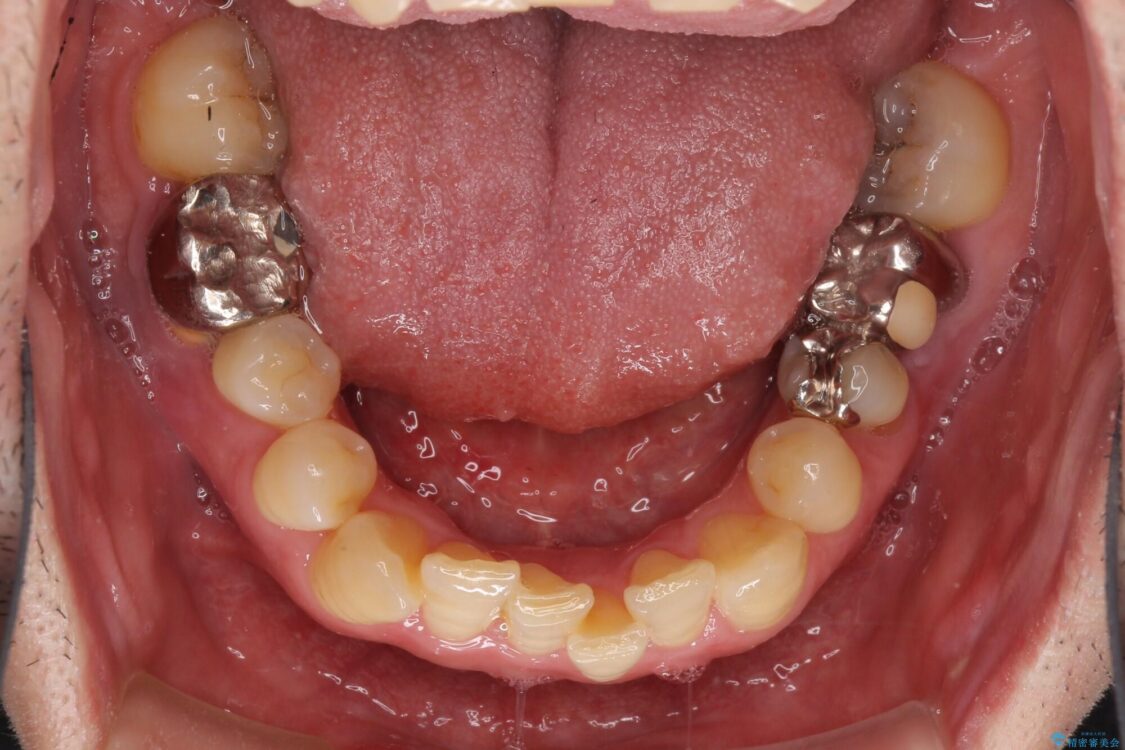

左右下顎の大臼歯は、ともに歯根が破折しており、抜歯が必要な状態でした。

放置したことで炎症による骨吸収が顕著であるため、骨造成を併用してインプラント埋入を行うこととしました。

治療前

• 割れてしまった奥歯とデコボコの前歯 矯正治療とインプラント治療 治療前画像